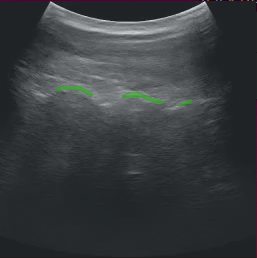

After modifying the application as instructed above, running the application should bring up the ultrasound video with a segmentation mask overlay similar to the image below.

Fig. 10 Ultrasound Segmentation